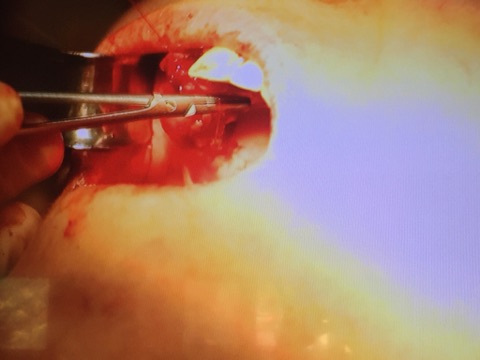

Мастер-класс начался с обсуждения предстоящей операции и снимка компьютерной томографии, после чего участники смогли присутствовать на операции.

После операции модератор провел обсуждение проведенной работы, теоретической основы и представил относящиеся к теме слайды.